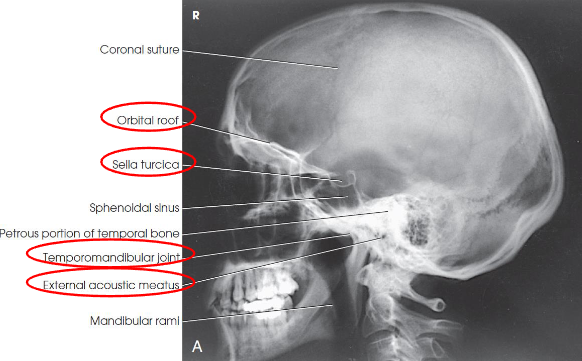

Lateral skull image criteria

entire cranium without rotation or tilt

superimposed orbital roofs and greater wings of sphenoid

superimposed mastoid regions, EAMs, and TMJs

sella turcica in profile

penetration of parietal region

no overlap of c-spine by mandible